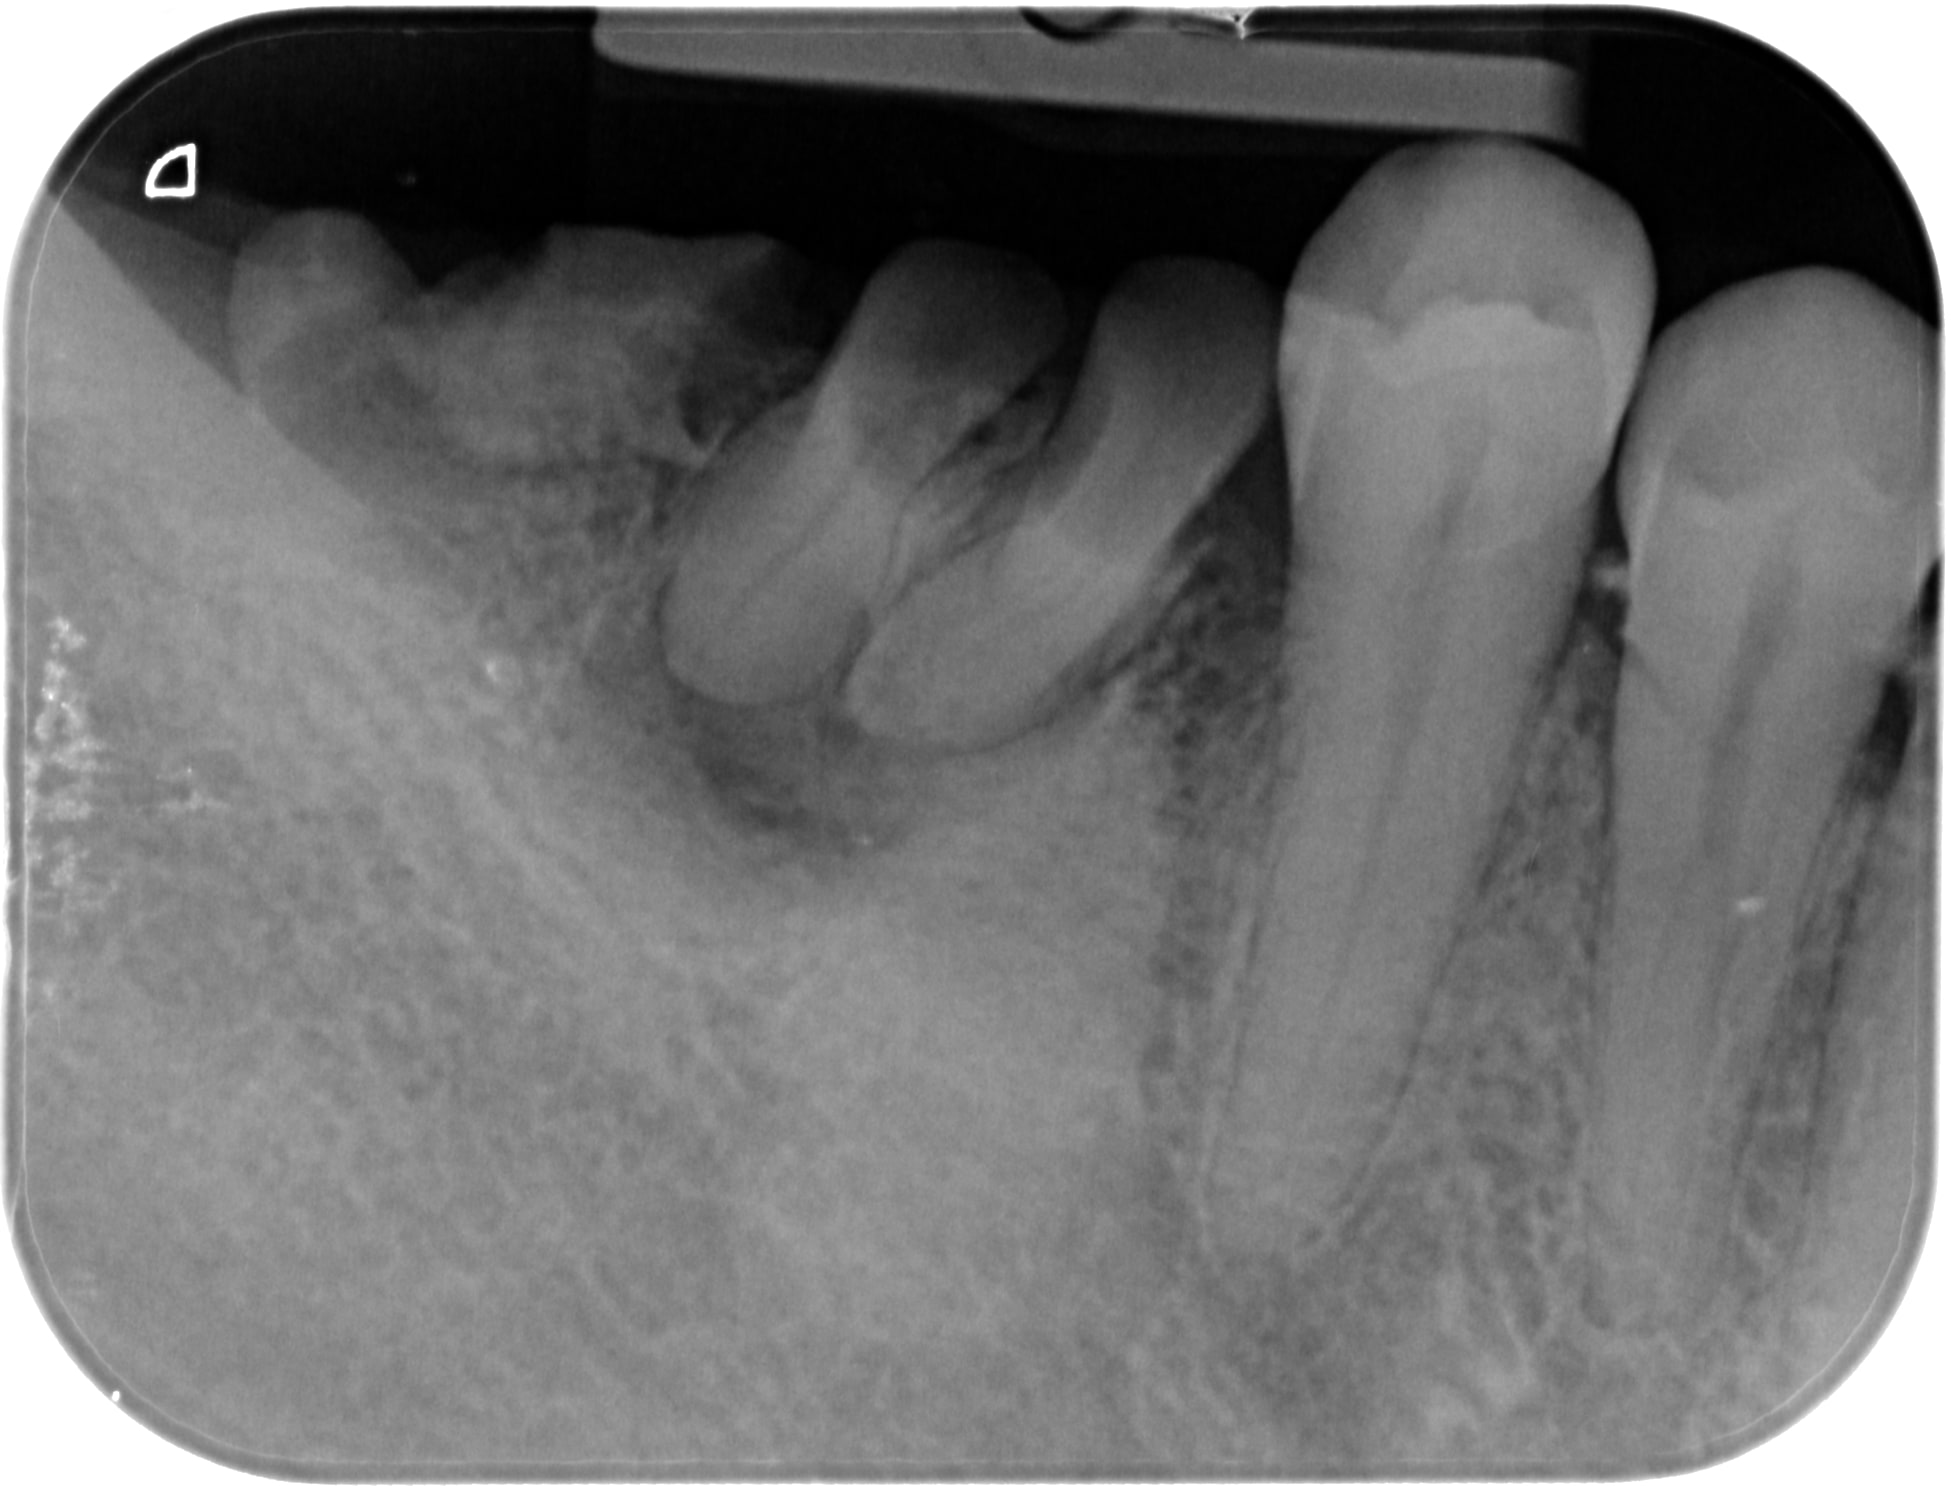

Des comme ça j'en 2 ou 3 par semaine (vu à l'instant ) ... Petite question : quel âge à ce patient ? Deuxième question à Carident et à quelques autres, quel est le montant de votre plan de traitement ? ( je ne demande pas le détail )(@ lardon , la 15 en métal , marqueur social ? ) .. troisième question : pensez vous que ce patient a la mutuelle adéquate à son état dentaire et enfin : pensez-vous que ce patient serait mieux pris en charge grâce au RAC 0 ? On va faire dans le concret de pas mal de cabinet dentaire ....

Pour l'age, c'est pas pour l'expulser, mais c'est impossible à dire par rapport à la radio. Au delà de 18 ans, c'est certain, tu ne sera pas arrêté pour détournement de mineur.

Puisque tu en parles, ca doit être la trentaine. Il a eut différentes extractions réalisées au cour du temps et à abandonné déjà les soins en cours de route.

C'est bien pour cela que c'est impossible de parler de devis et de tarifs, puisque quelque soit le devis, les probabilités d'arriver au bout du plan de traitement sont faible et il abandonnera bien avant les prothèses sur des soins opposables ce qui montre que le tarif et les remboursements ne sont pas en cause.

26/02/2018 à 12h12

Age 19 Ans ! , et bien sûr qu'il ira au bout du traitement s' il peut financièrement ! Il est motivé , c'est un jeune homme "bien" . sérieux , il est à l'heure , n'est pas peureux .. bref , ce genre de patient où tu sais pertinemment que ce qui va coincer c'est l'argent . Barba , il existe des patients non serieux à tous les niveaux de la société et quand c'est un cadre , là , on pense qu'il n'a pas le temps . Alors , on fait quoi pour ce jeune , on le prend en charge ( nous la société ...) ? on lui dit que c'est trop tard ? t'avais qu'à te brosser les dents ? ( vous avez remarqué qu'il a eu déjà de nombreux soins ) . Et, s'il vous plait, gardez pour vous vos généralisations à 2 balles ! ( barba , tu me suis ? ) . Ah ouais aussi , je ne lui ai pas mis un devis sous le nez avant de commencer à le soigner .. évidemment !

Je précise aussi , ce patient n'est pas venu parce qu'il avait mal .... étrange , non ?